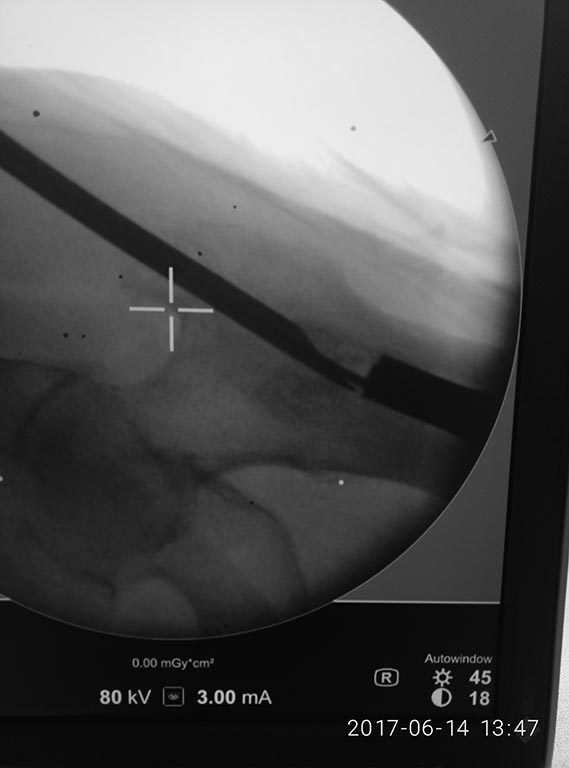

Доброе утро, коллеги! Фикшен с бедра удалили, сидел очень плотно.

На ортопедическом столе уложили, ногу согнули, как на ретроградное

бедро, артротомия, релиз 4-главой, увеличили обьем движений. Далее

попытка выбить плечевым, голенным штифтом не сильно имела успех. Стоял

на своем. Проксимально по направителю рассверлили канал развертками

11,12. В итоге взяли 11 фемор санатметал, несколько ударов, и он вылетел

из бедра!